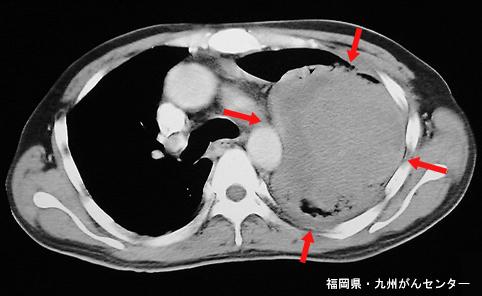

症例提示(所在地,施設名等): 福岡県・ 九州がんセンター

症例登録日 2002/10/21

性別 男性

年齢 50-54

部位(臓器別)その他/

検査方法CT

病変の最大径(ミリ)40以上